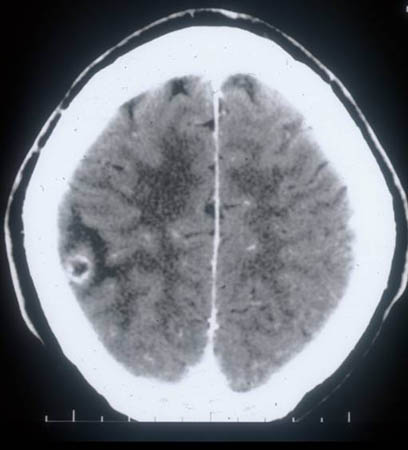

Colloidal stage - neurocysticercosis: CT scan showing ring enhancing cystic lesion in the temporal lobe and perilesional oedema

From the personal collections of Dr Christina Coyle and Dr Maheen Saeed; used with permission